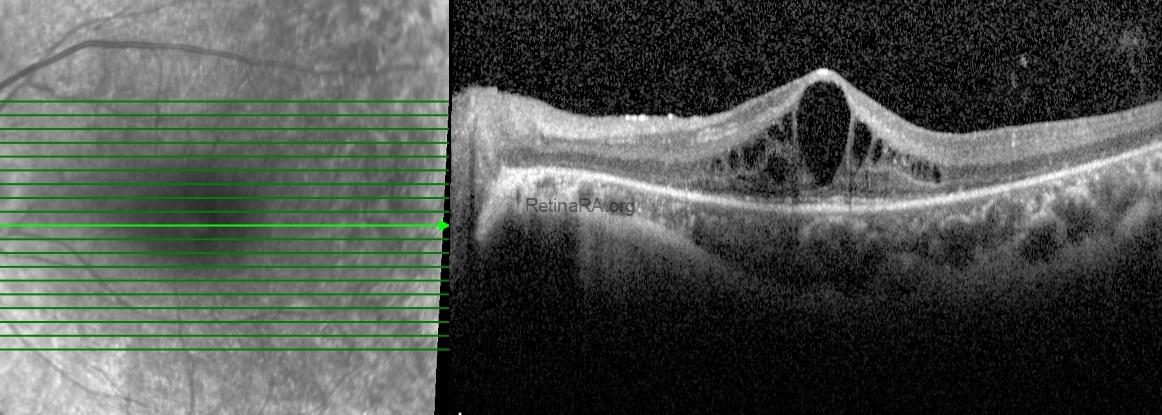

Spectral-domain optical coherence tomography of the macula demonstrated pronounced outer retinal atrophy, with disruption and loss of the ellipsoid zone. In addition, multiple intraretinal cystic spaces were present in the foveal and parafoveal regions, consistent with cystic macular edema. Structural alterations of the outer retina and the retinal pigment epithelium complex were also noted.

Based on the clinical and imaging findings, a diagnosis of retinitis pigmentosa with macular involvement was made. The coexistence of advanced outer retinal degeneration and cystic macular edema was considered the main contributing factor to the patient’s reduced central visual acuity.